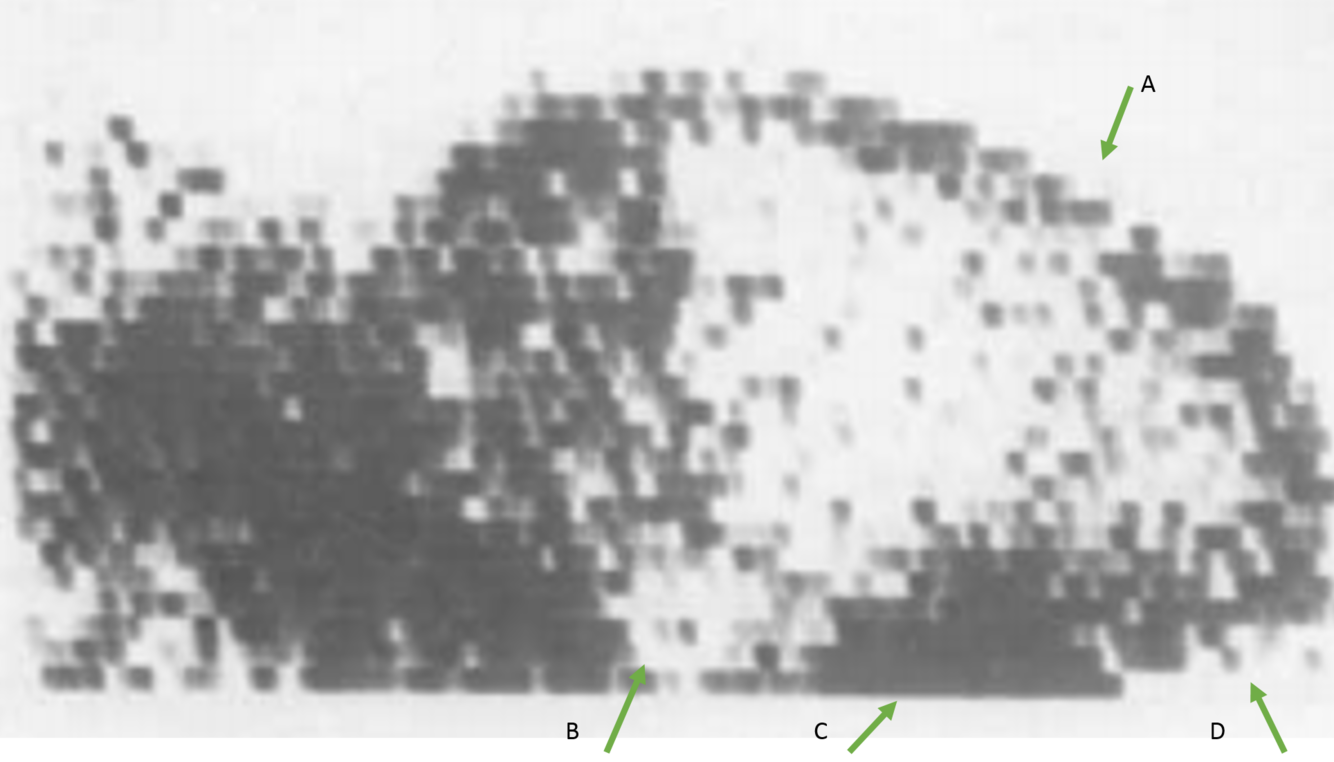

Lateral scan of a normal brain

A: vasculature of the scalp, underlying sheel, dorsal longitudinal sinus - progressively wider band coursing caudally

B: Nasopharynx - circular region of decreased activity

C: Parotid salivary gland

D: Transverse sinus courses in a rostroventral direction